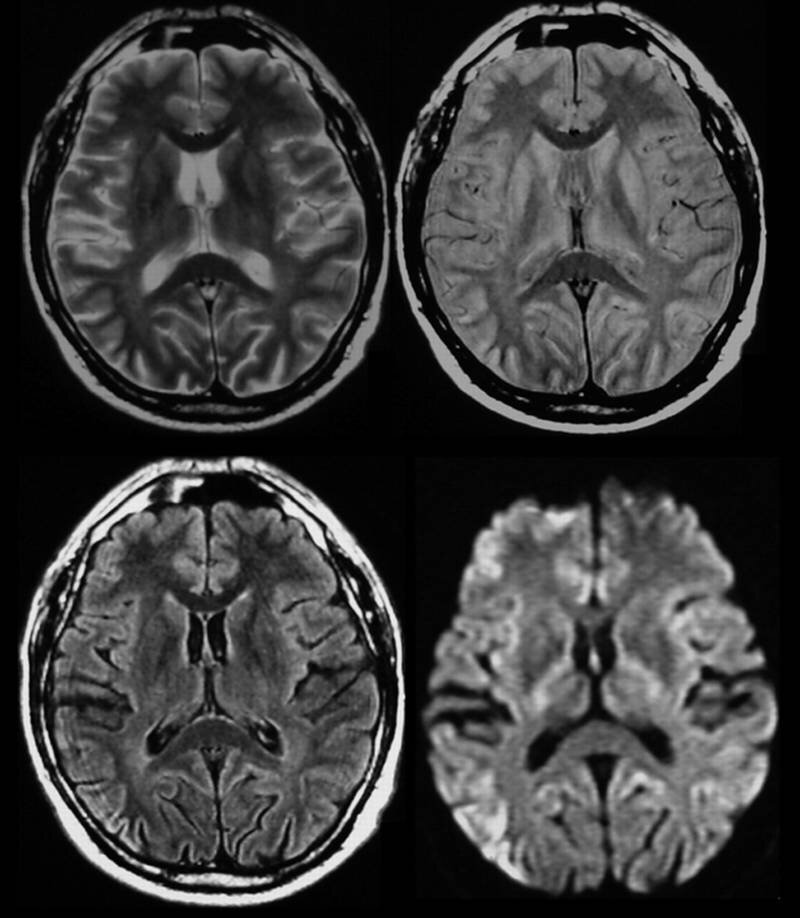

Как правило если такой пациент поступает в клинику, то первый диагноз, который приходит в голову - острое нарушение мозгового кровообращения, другими словами инсульт.

В таких случая полагается быстро провести нейровизуализацию с помощью компьютерной томографии или МРТ.

Ему было выполнено МРТ, которая к удивлению врачей дала неожиданные результаты. Изменения головного мозга не были похожи на те, которые возникают при инсульте.

Это было что-то новое и непонятное. Полистав литературу, врачи пришли к выводу, что столкнулись с крайне редким заболеванием - болезнь Крейтцфельдта-Якоба. Это был 5 случай, зарегистрированный в США.